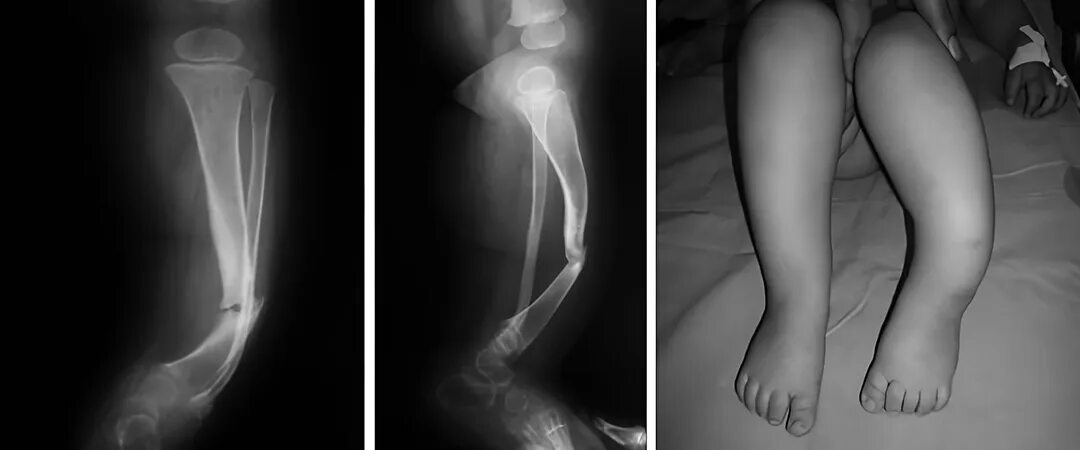

Не срастается сустав